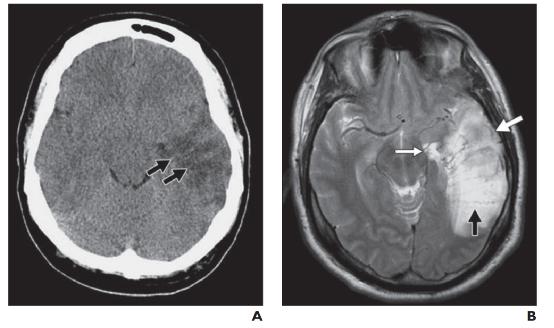

急性动脉梗塞会产生缺氧状态,伴随去极化、炎症、氧化或亚硝化应激以及细胞凋亡继发的 ATP 快速消耗。细胞毒性水肿在动脉闭塞后 30 分钟内出现,在梗塞后 24 至 72 小时达到峰值,并在再灌注后持续长达 24 小时。在 CT 上,灰白质界限的丧失发生在对应的血管分布位置。大脑中动脉梗死的早期迹象包括豆状核的遮蔽(图 1A )) 和岛带的丢失 (图 1B); 这些通常具有高灰白对比度的区域由小的脑动脉穿支供血。大的血管内血栓也可能表现为类似增强扫描的密度增高(高密度动脉征)(图 1C )。进行性水肿导致病灶整体体积增加,表现为脑沟、脑室和脑池的消失。

图 1A —大脑中动脉 (MCA) 梗塞。早期 MCA 梗死的平扫 CT 图像显示右侧豆状核轻微水肿,豆状核由壳核(白色箭头)和苍白球(黑色箭头)组成。

图 1B —大脑中动脉 (MCA) 梗塞。亚急性 MCA 梗塞的平扫 CT 图像显示细胞毒性水肿,导致左侧岛叶带缺失(箭头)。

图 1C —大脑中动脉 (MCA) 梗塞。平扫 CT 图像显示右侧 MCA 高密度征(箭头)。